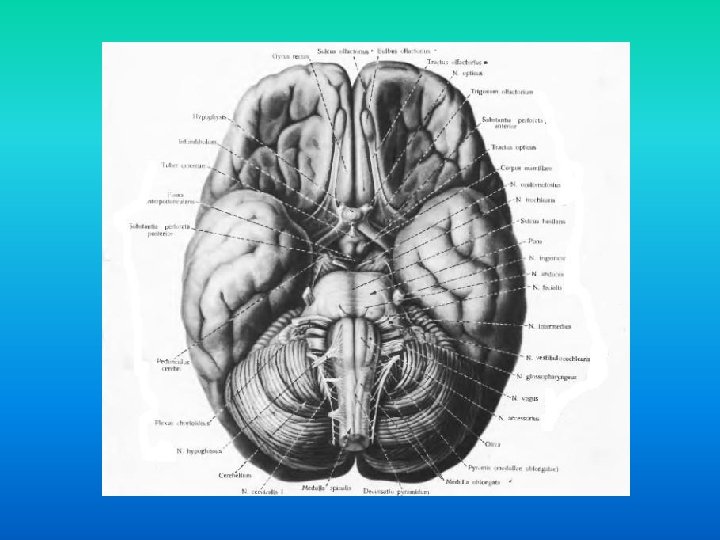

Tehnici de explorare radioimagistica n in functie de bazele fizice sunt: n tehnici ce utilizeaza razele X: n n radiografii, mielografii, CT tehnici imagistice ce utilizeaza alte modalitati de obiectivare a structurilor anatomice: n ecografia, IRM

n Patologiile localizate in regiunea sella turcica ocupa un rol aparte in patologiile intracraniene din cauza structurilor de importanta vitala situate in regiune: • Hipofiza. Arterele carotide (si implicit inelul arterial al creerului). Sinusul cavernos (+ nervii cranieni). Chiasma optica (0. 5 cm supraselar). • • •